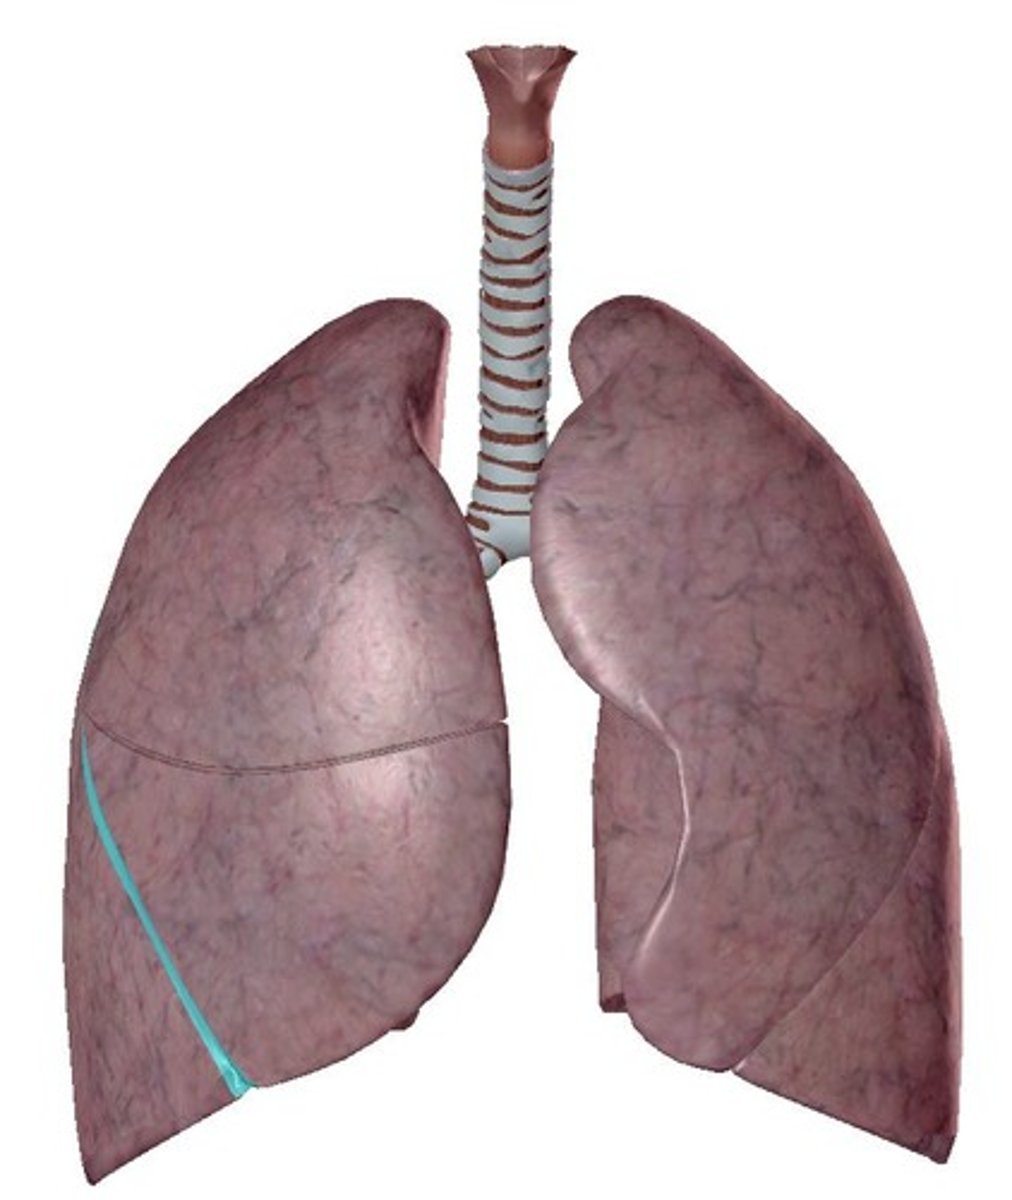

fissure

separates lobes in each lung

horizontal fissure

separates the superior and middle lobes of the right lung

right oblique fissure

separates the right middle and inferior lobes

left oblique fissure

separates the superior and inferior lobes of the left lung